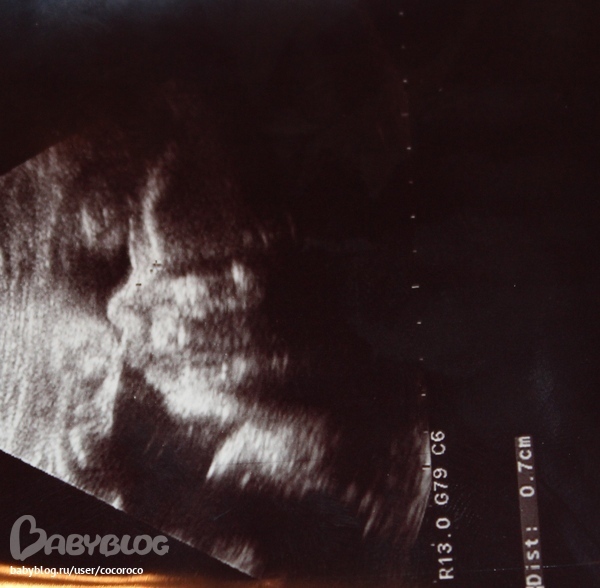

Врач сказал норма в весе,на этом сроке 1300 а у нас 1622))) Рост норма 37 а мой сынок ростом 38 )

Всю ночь,после дня рождения болел живот!!!!!!!Думала умру уже((((((( Боли приступами!(( Потом жилудок болел!!!Короче то ли и то и другое болела,я так и не поняла!!!!!!Видема набегалась с гостями!Приезжали родители мои,мужа..А я давай наготовила,бегала тут!В итоге всю. ночь не спалА ОТ БОЛИ!(((( Блин так испугалась!(( В итоге с утра поехали на узи,все слава Богу хорошо!Надо лежать пару дней,дома!(

Это начало 26 недели было, мне кажется мы не маленькие))Просто смотрю тут девочки такие миниатюрные))